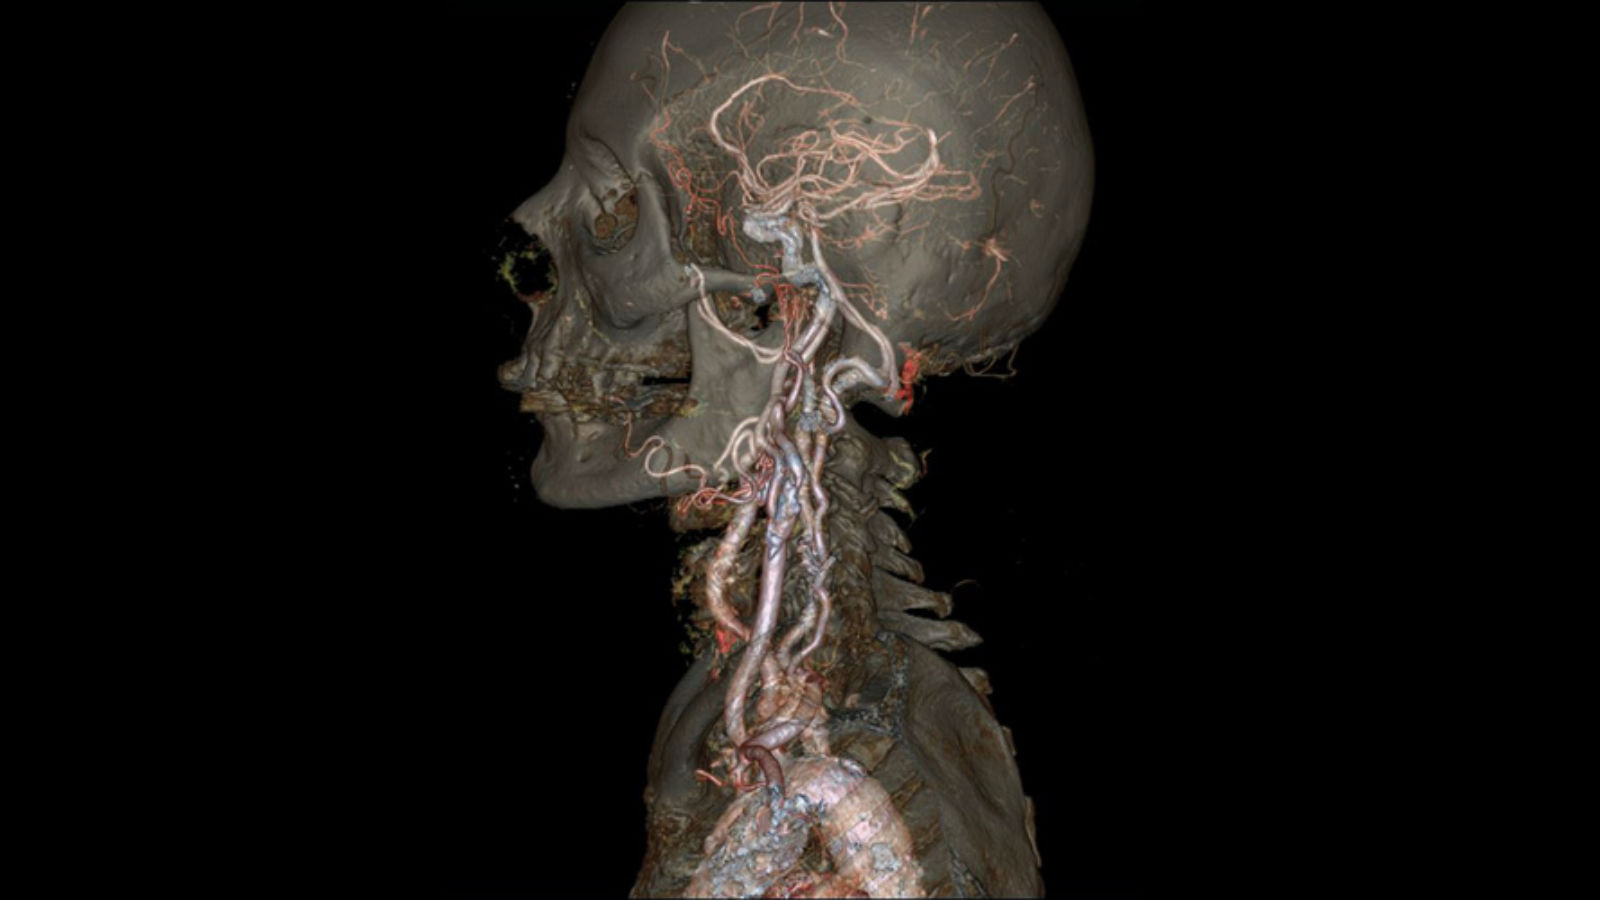

sjra.comInterior imaging uc scanner. Ct scan wallpapers. Ct scan wallpapers

sjra.comInterior imaging uc scanner. Ct scan wallpapers. Ct scan wallpapers